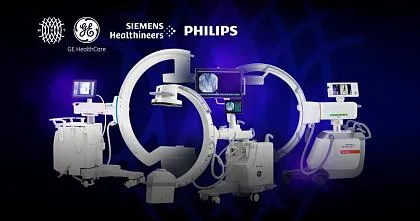

Официальный дистрибьютор GE HealthСare с 2007 года

Каталог

Официальный дистрибьютор MINDRAY

Каталог